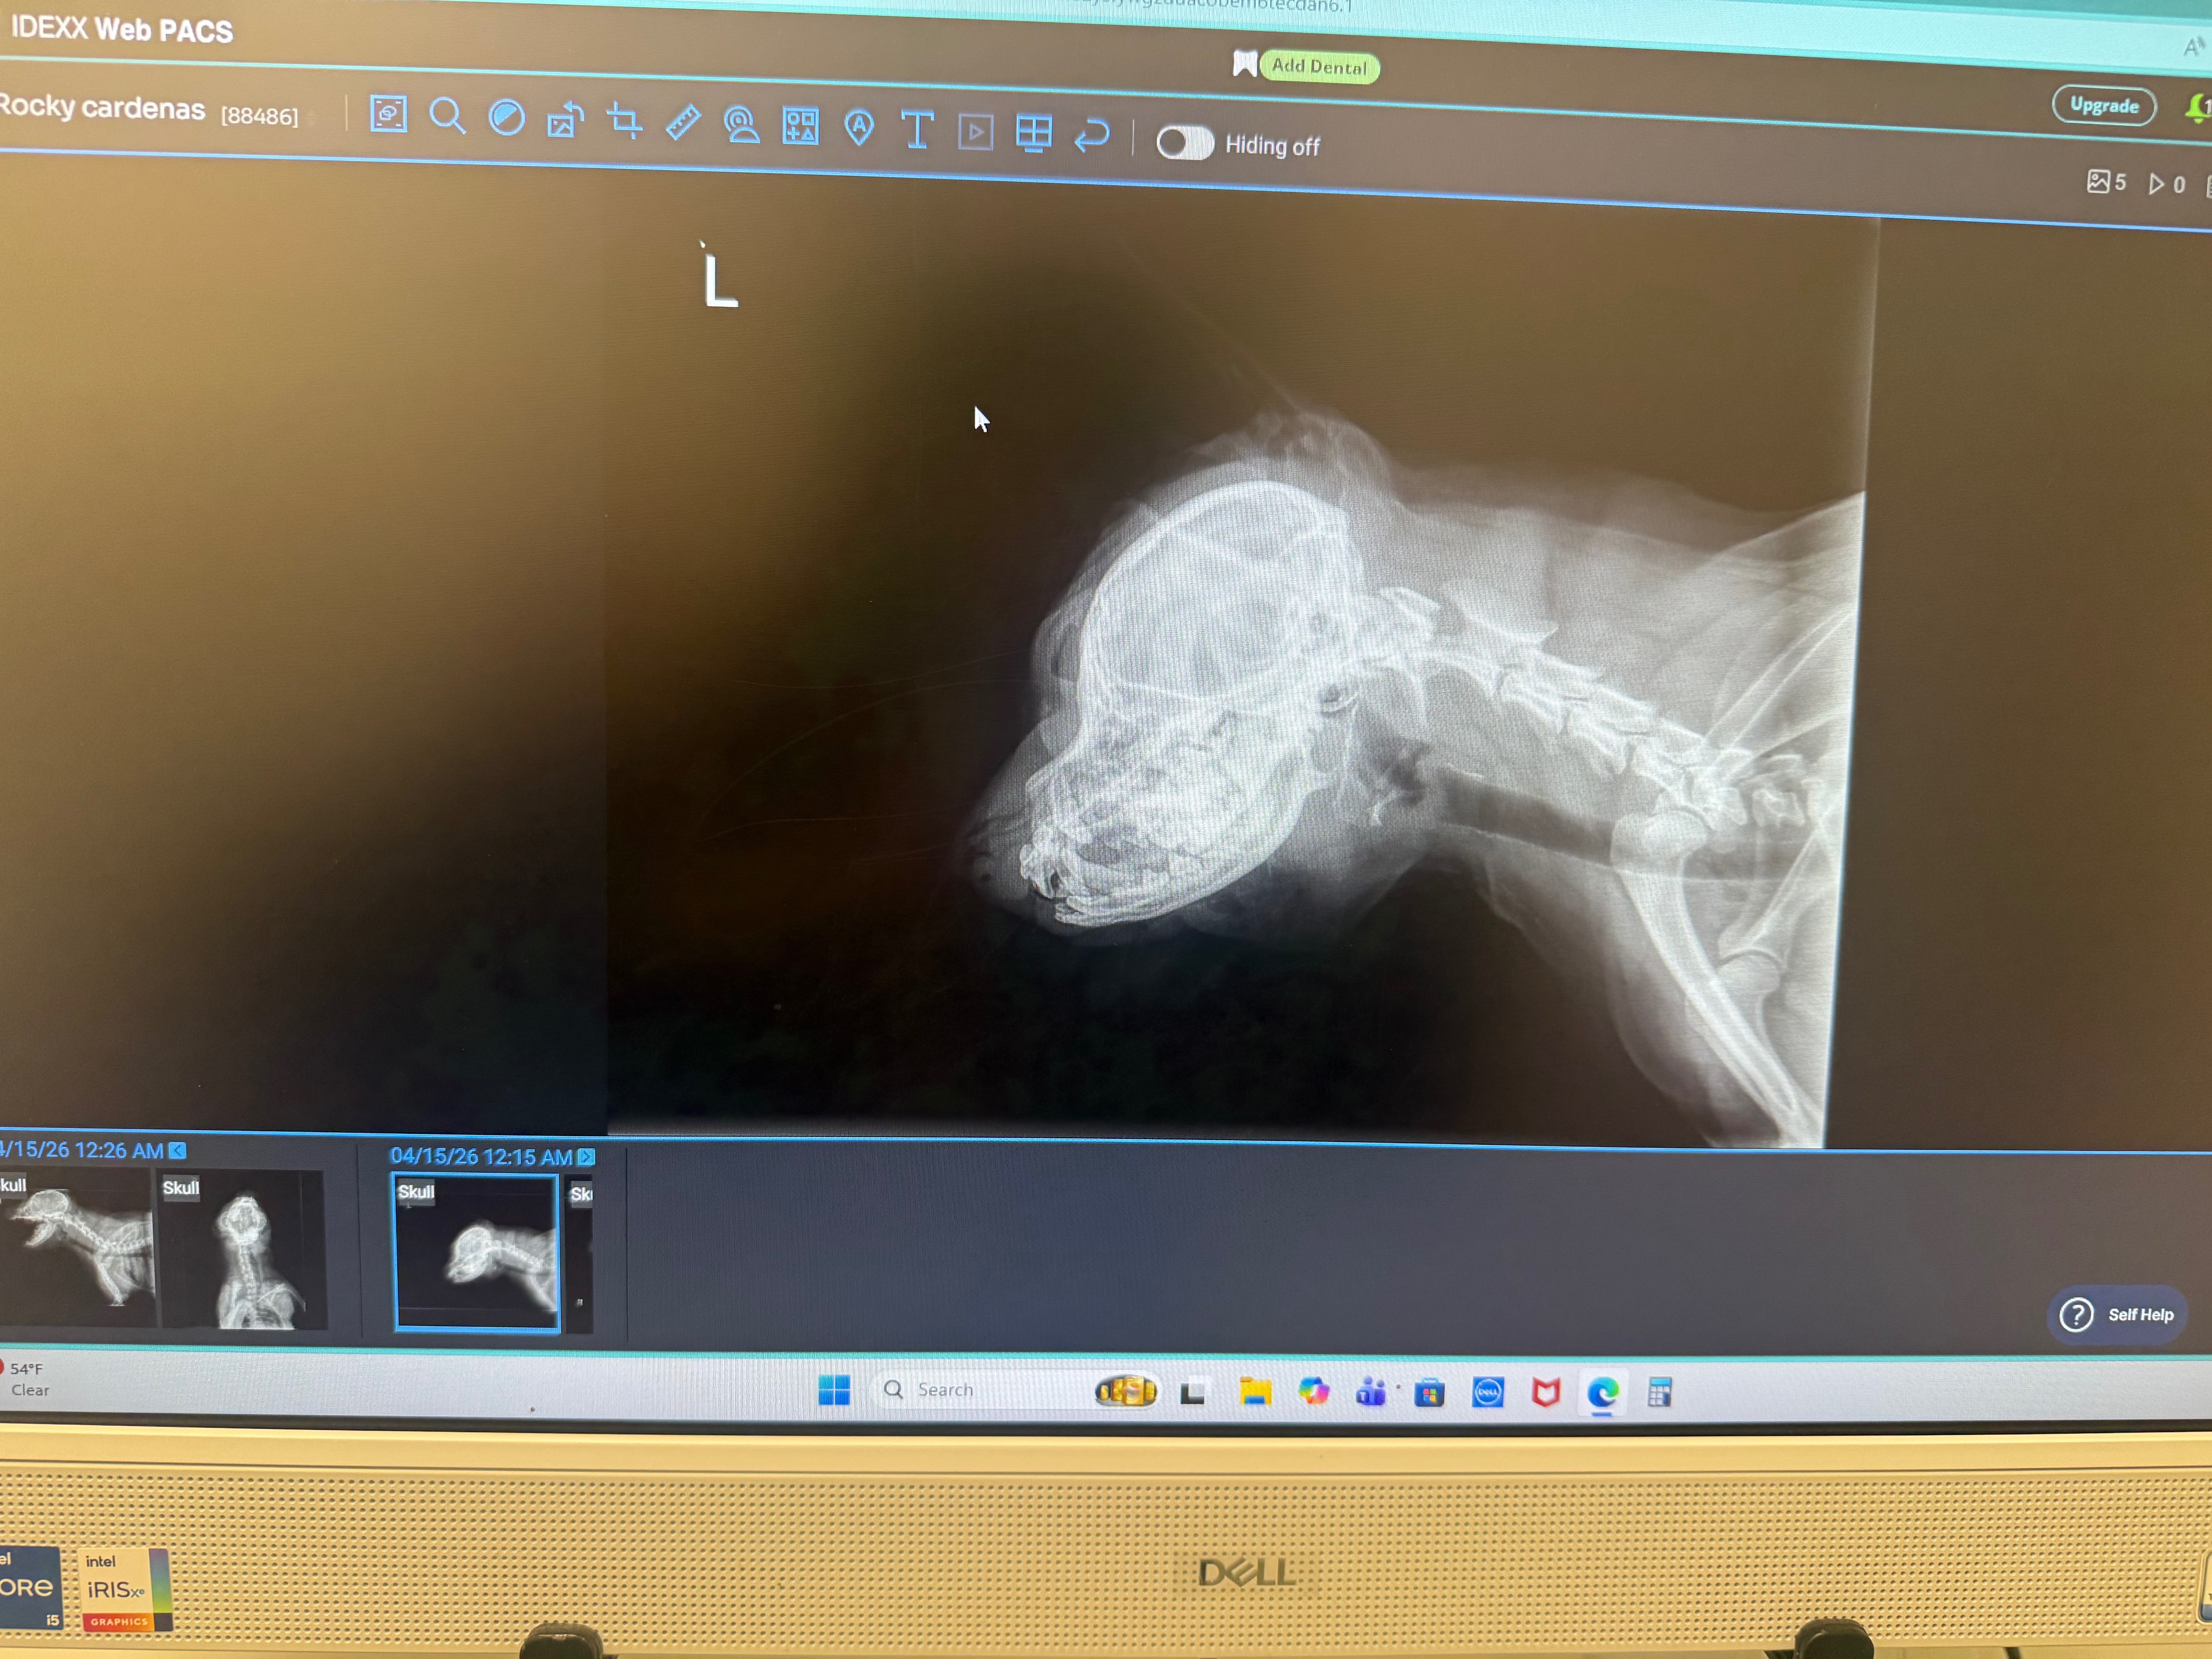

I’m reaching out with a heavy heart to ask for help for my puppy, Rocky. He was recently attacked by another dog, and as a result, his jaw has been severely dislocated. He is in a lot of pain and needs emergency surgery as soon as possible.

it’s heartbreaking to see him like this. He hasn’t been able to eat properly and is struggling due to the injury.